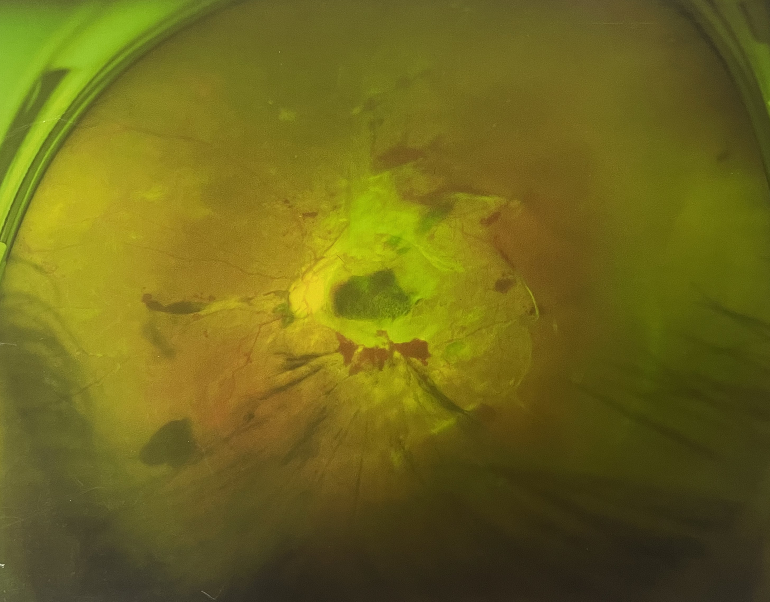

4個月前的左眼

左眼發(fā)展到糖尿病視網(wǎng)膜病變VI期

由于王女士的左眼沒有聽從醫(yī)生盡快做手術(shù)的建議,一直耽誤,從4月前的0.4視力逐漸下降到僅剩眼前手動,導(dǎo)致左眼發(fā)展到糖尿病視網(wǎng)膜病變VI期(屬于6期糖網(wǎng)中的晚期),已經(jīng)產(chǎn)生大量新生血管+纖維增值+廣泛牽拉性視網(wǎng)膜脫離,由于耽誤了病情,且病情發(fā)展異常迅速,導(dǎo)致目前左眼連保住眼球都很困難。

“而如果4月余前,左眼及時手術(shù)(當(dāng)時左眼病情比右眼輕,增殖膜還未累及黃斑),左眼將恢復(fù)的比右眼還好,甚至可以恢復(fù)到0.8或1.0,而現(xiàn)在連保住眼球的機(jī)會都很渺茫”,張小虎醫(yī)生表示實在可惜。